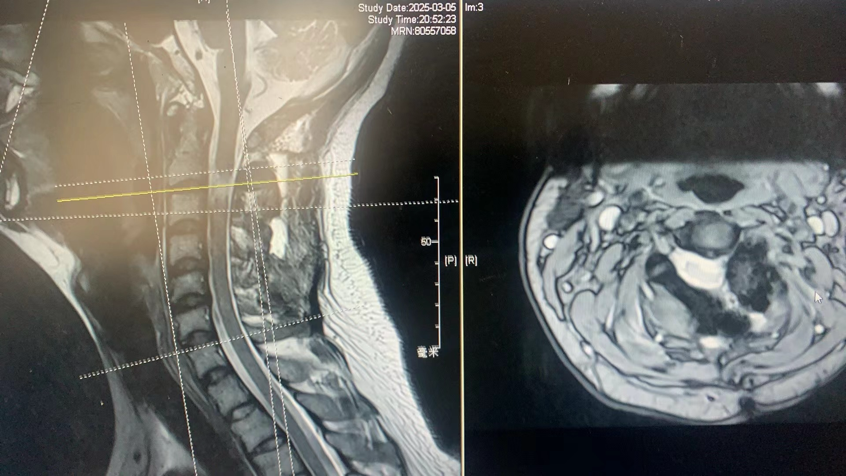

经过检查,他被诊断为颈2/3节段哑铃型神经鞘瘤,肿瘤严重压迫脊髓的右侧并从脊髓腹侧侵犯到左侧,随时可能造成不可逆的瘫痪。

高位颈2/3哑铃型肿瘤

从左侧经脊髓腹侧延伸到右侧压迫脊髓

手术后核磁共振证明肿瘤完全切除,脊髓恢复,没有脑脊液漏